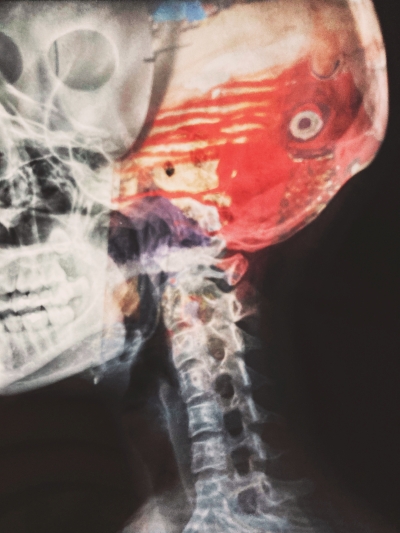

우리나라에서 단일 질환으로 사망률 1위는 뇌졸중이라고 하는데요. 뇌졸중은 뇌의 혈관이 좁아지면서 혈관이 막히며 발생하는 질환입니다.

뇌졸중 예방

단 몇 분만 뇌에 혈액이 공급되지 않아도 뇌 세포는 손상됩니다. 한번 손상된 뇌세포는 다시 살릴 수 없으므로 빠른 대처가 가장 중요한 질병입니다.